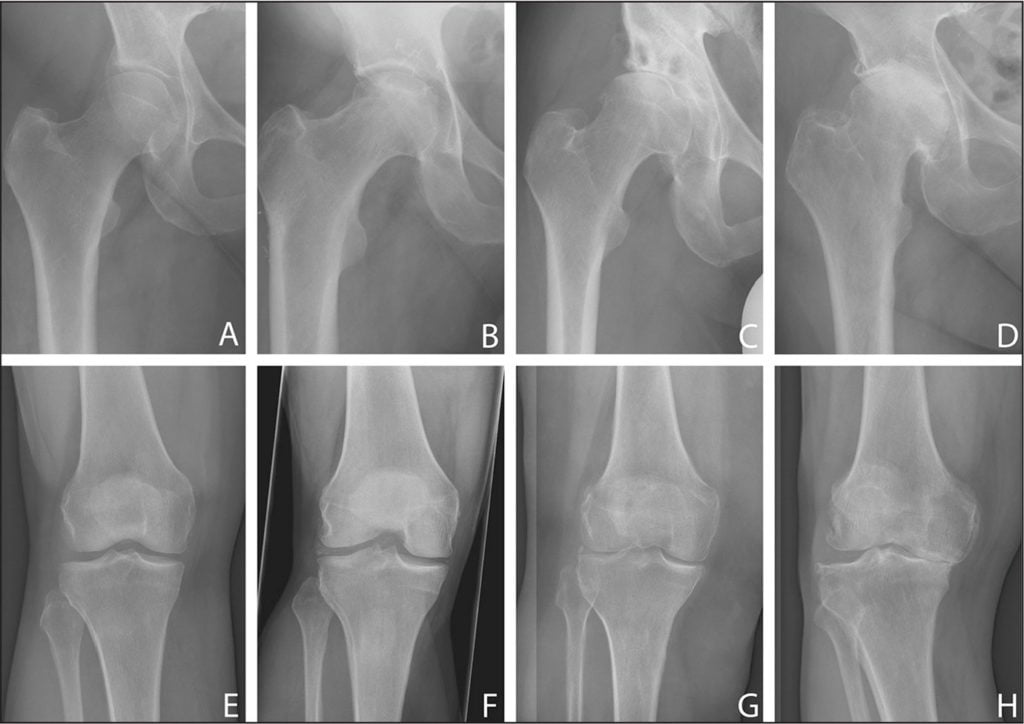

| 1 степень | Это легкая форма болезни, которая проще всего поддается лечебной терапии. Наблюдаются периодические боли в бедре, чаще после физических нагрузок.Нет заметной деформации сустава либо хромоты, поэтому люди часто не спешат с обращением к врачу. На снимках рентгена врач может заметить только небольшое сужение суставной щели |

| 3 степень | Самая тяжелая стадия: полное разрушение хряща, острые боли, отеки тканей, нормальное передвижение невозможно.На снимках рентгена видны критическое сужение просвета между костями, деформирование сустава. Лечение — обычно хирургическое |

- Рентгенография поможет выявить наличие остеофитов, области окостенения хряща, остеопороз, определить степень сужения суставной щели.